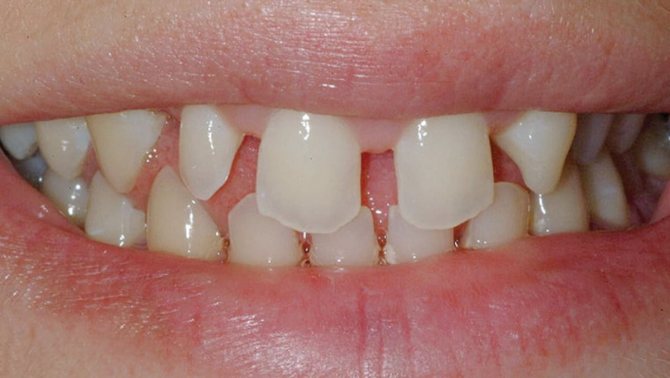

Если зубы располагаются друг от друга на слишком большом расстоянии, то такое состояние называют диастемой. Дефект чаще наблюдается между передними зубами.

Диастема — щель между зубами

Данная патология представляет собой промежуток между фронтальными резцами. В большинстве случаев проблема возникает на верхней челюсти.

Диастема бывает настоящей и ненастоящей. Первая появляется, как результат попадания волокон соединительной ткани уздечки губы в срединный шов. Вторая возникает во время смены зубов, проходит самостоятельно по окончании выхода наружу клыков и боковых резцов.

Данный недуг классифицируется также по Ф.Я. Хорошилкиной, которая выделила первый, второй и третий тип диастемы.

Разновидности диастемы

Первый – отклонение латерального типа фронтальных центральных коронок при норме расположения корней. Основанием для подобной формы служит сверхкомплектность, постоянное сосание языка и пальцев.

Второй – корпусное латеральное отклонение резцов от нормы. К факторам развития относится адентия боковых зубов, излишняя плотность костной ткани, расположенной по срединному шву, дистальное формирование клыков, резцов, низкая фиксация уздечки верхней губы. Диастема второго типа часто носит наследственный характер.

Третий – серединный наклон фронтальных коронок и их латеральное отклонение в отношении корней. Такой вид проявляется при лишних зубах, многокостной адентии.

Коронки при диастеме размещаются следующим образом:

- Без поворота.

- С поворотом вокруг себя в вестибулярную сторону.

- С поворотом в оральную сторону.

Щель между зубами не так безобидна, как кажется. Она приводит к дефектам речи, сложности произнесения некоторых согласных звуков, а также влечет за собой пародонтопатию ввиду ослабления стойкости зубов.

Для устранения проблемы используются ортодонтические конструкции или комплексное лечение хирургическо-ортодонтической направленности.